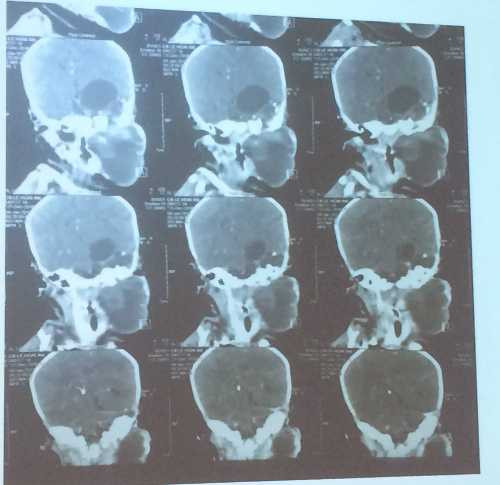

Hình ảnh khối bướu lan từ vùng cổ lên não

Bác sĩ Phan Minh Trí, Khoa Ngoại Tổng hợp cho biết bệnh nhi vào viện lúc 20 ngày tuổi với khối bướu ở góc hàm bên trái. Kiểm tra cho thấy khối u nằm từ góc hàm lan lên vùng nội sọ. Các bác sĩ đã hội chẩn toàn viện để thống nhất phương án phẫu thuật lấy khối bướu ra, giải thoát bé gái khỏi nguy cơ chèn ép đường thở, thực quản, chèn ép não dẫn đến tử vong.

Bác sĩ Đào Trung Hiếu, Phó giám đốc Bệnh viện Nhi đồng 1 cho biết khối bướu quái vừa là mô đặc vừa chứa dịch, thậm chí có cả xương, tóc. Bướu quái thường gặp ở cơ quan sinh dục như buồng trứng, tinh hoàn, vùng xương cùng cụt, trong lồng ngực… Bướu quái vùng cổ hoặc vùng sọ cũng khá hiếm gặp, còn trường hợp kết hợp cả hai, lan từ cổ lên vùng sọ thế này là cực kỳ hy hữu.